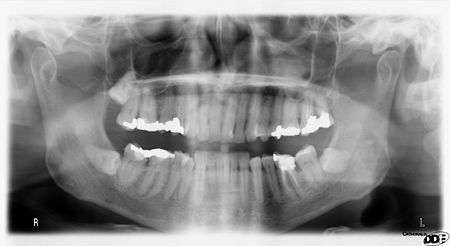

Dental Radiographs are commonly called x-rays. Dentists use radiographs for many reasons: to find hidden dental structures, malignant or benign masses, bone loss, and cavities.

A radiographic image is formed by a controlled burst of X-ray radiation which penetrates oral structures at different levels, depending on varying anatomical densities, before striking the film or sensor. Teeth appear lighter because less radiation penetrates them to reach the film. Dental caries, infections and other changes in the bone density, and the periodontal ligament, appear darker because X-rays readily penetrate these less dense structures. Dental restorations (fillings, crowns) may appear lighter or darker, depending on the density of the material.

It is possible for both tooth decay and periodontal disease to be missed during a clinical exam, and radiographic evaluation of the dental and periodontal tissues is a critical segment of the comprehensive oral examination. The photographic montage at right depicts a situation in which extensive decay had been overlooked by a number of dentists prior to radiographic evaluation